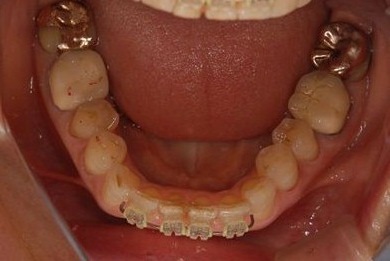

部分矯正治療+セラミック治療

| 性別/年齢 | 女性 / 54歳 | ||||||||||||||||||||||||||||||||

| 主訴 | 下の前歯のゆがみが気になり、相談。 | ||||||||||||||||||||||||||||||||

| 治療方針 | 上顎前歯の叢生を部分矯正にて審美的回復を行い、上顎前歯はラミネートベニアにて審美的回復を行う。 | ||||||||||||||||||||||||||||||||

| 治療内容 | 唇側部分矯正(ホワイト)、オールセラミックラミネートベニア8本 | ||||||||||||||||||||||||||||||||